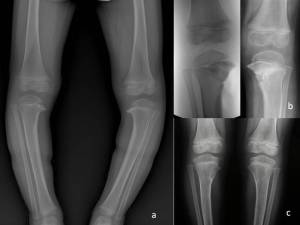

- Fig. 13: A) Anni 4, morbo di Blount bilaterale. B) Aspetto clinico dopo 2 anni dall’intervento di osteotomia.

- Fig. 14: A) Aspetto radiografico del paziente in fig 13. B) Intervento di osteotomia di sollevamento del piatto tibiale bilaterale. C) Controllo RX dopo 2 anni.

Esiste anche una forma ad insorgenza tardiva detta Blount giovanile (fig 15): anche in questi casi, se la deformità mostra tendenza al peggioramento, occorre eseguire un’osteotomia associata eventualmente ad una epifisiodesi temporanea laterale.